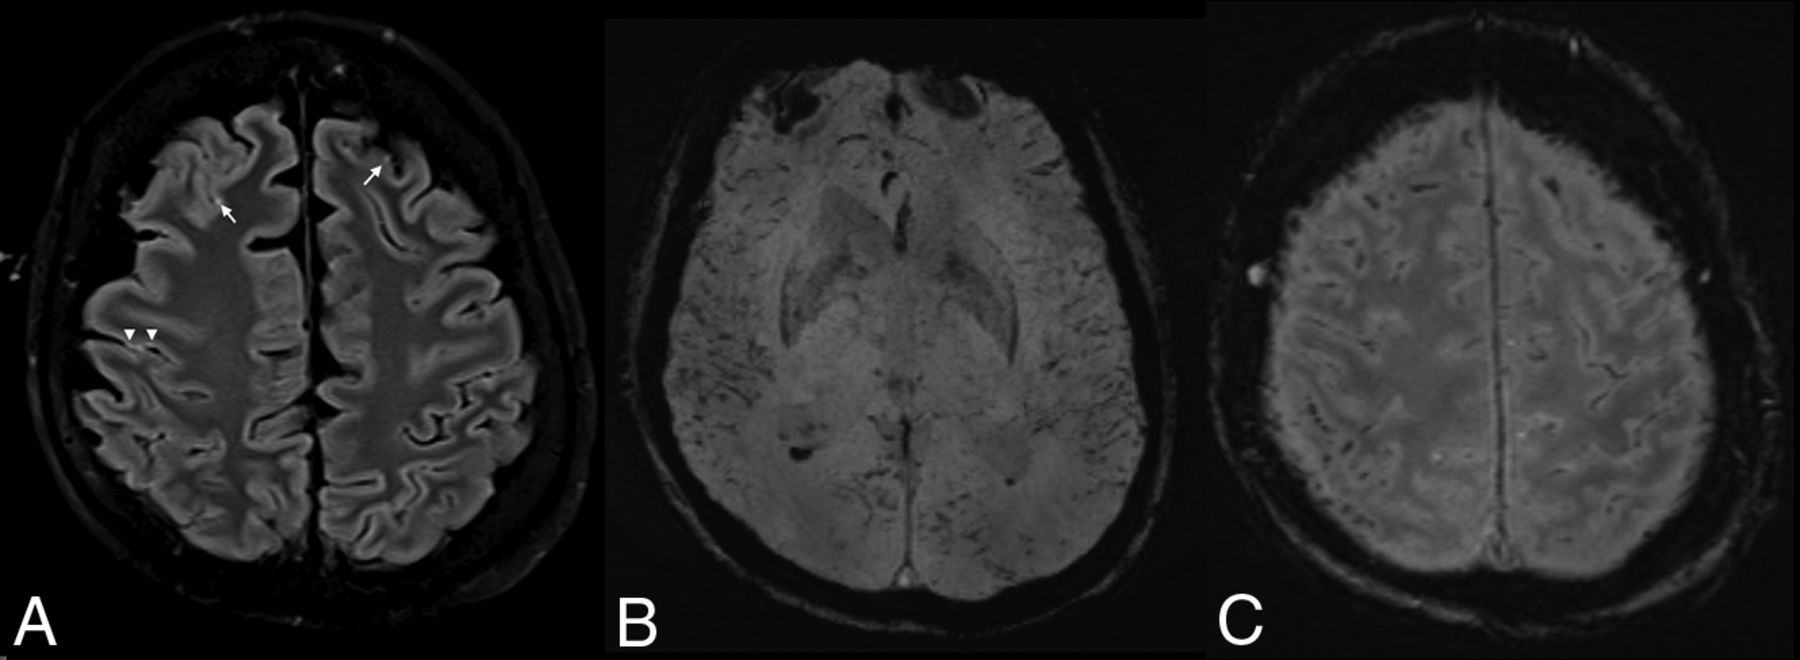

A 57-year-old man also underwent ECMO for respiratory failure. Following extubation, the patient demonstrated altered mental status and right-arm weakness. A CT scan (Fig 2) also showed multiple subcortical and subpial petechial hemorrhages. MR imaging, limited by motion artifacts (Fig 2B, -C), showed extensive petechial hemorrhages on SWI with some breakthrough small-volume parenchymal hematomas. There was also extensive parenchymal SWI abnormality, which appeared to correlate with a venular distribution and was predominantly in a subcortical pattern (as opposed, for example, to the deep gray matter SWI microhemorrhages, which can be seen in patients with hypertension). This subcortical SWI abnormality was not confined to 1 lobe of the brain but was rather more diffuse. The DWI sequences showed a few scattered multifocal cortical infarcts, but the areas of abnormal subcortical SWI signal showed no DWI abnormality. There was no significant T2/FLAIR edema, and no mass effect or sulcal effacement in these regions. His white blood cell count was 16.3 × 109/L, and his D-dimer level exceeded 4400 μg/L. His platelet count was also in the normal range (174 × 109/L). His activated partial thromboplastin time was elevated at 63.7 seconds, as well as his prothrombin time (12.2 seconds) and his serum ferritin level (4287 μg/L).

Patient 2. A, CT scan shows multiple subcortical and subpial petechial hemorrhages. B and C, MR imaging, limited by motion artifacts. B, Susceptibility-weighted axial image shows extensive SWI abnormality C, T1 sagittal, noncontrast image shows some breakthrough macroscopic parenchymal hematomas.